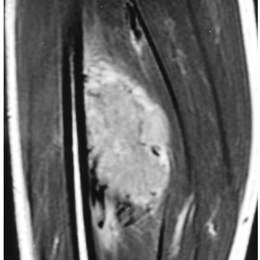

Radiographic imaging is used to help form a diagnosis. These include MRI, CT and Bone Scans.

An example of an MRI is shown.